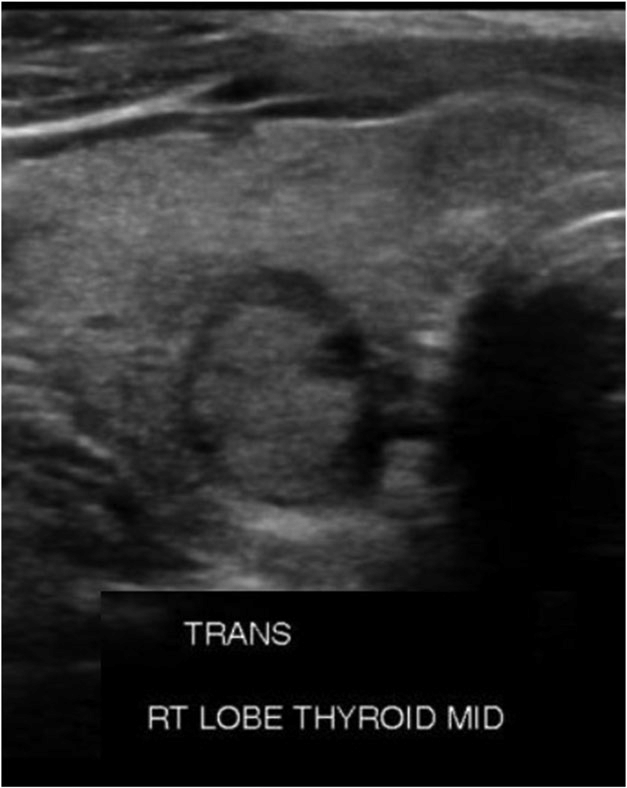

침상 또는 소엽성 경계(spicu lated or lobulated margin) : 결절의 경계가 매끄럽고 둥글지 않으며 뾰족한 바늘처럼 튀어나와 있거나 울퉁불퉁한 것을 말합니다.

세로길이(taller than wide):결절이 가로로 긴 것이 아니라 마치 위에 서 있는 것처럼 위아래가 긴 모양을 말합니다.

저에코(hypoechogenic n odule) : 초음파에서 다른 조직에 비해 더 어두워 보이는 병변을 말합니다.